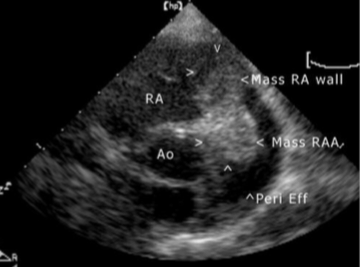

Thoracic Tumors Heart Dr Julius Liptak

Thoracic Tumors Heart Dr Julius Liptak from images.squarespace-cdn.com